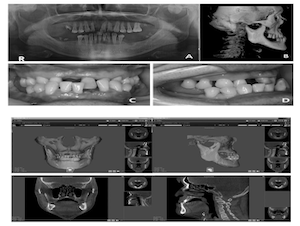

Contour Restoration of Over- Resected Mandibular Angle and Lower Border by Reduction Mandibuloplasty Using Three- Dimensional Planning and Computer-Aided Design and Manufacturing Custom-Made Titanium Implants

Prof. Jin Young Choi,orthognathic surgery,Mandibular,contour restoration,FACEGIDE,R2GATE,Digital orthognathics,CAD/CAM,mandible augmentation,over-resection, restoration of contour,titanium implant,virtual surgery,2jaw,Division of oral and Maxillofacial surgery,wafer,saw-guide,face-plate,customized,osteotomy,lefort1,bssro,Publication